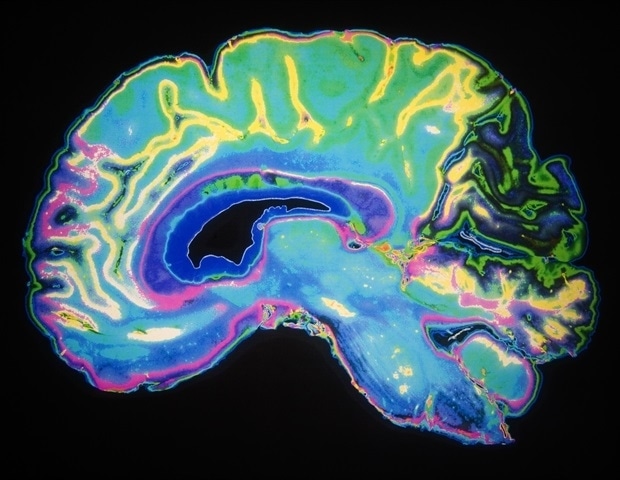

Основываясь на многолетнем наследии инноваций в Центре реанимационных исследований Питта Сафара, новое исследование дополняет растущие знания о биомаркерах ЧМТ у детей. В своем исследовании команда сосредоточилась на модификациях нейротрофического фактора головного мозга. (BDNF) из-за его роли в нейропластичности, то есть способности мозга к реорганизации и заживлению после травмы. Предыдущие исследования связывали уровни BDNF с результатами восстановления после ЧМТ у взрослых, но до сих пор ни одна группа не изучала его эпигенетические модификации у детей.

Сосредоточив внимание на одном из наиболее широко изученных типов эпигенетических модификаций - метилировании ДНК, исследователи смогли проанализировать, являются ли уровни метилирования BDNF. могут служить динамическими биомаркерами, которые отражают как биологические, так и психосоциальные факторы, влияющие на выздоровление, предлагая уникальную молекулярную линзу для детской ЧМТ.

Ученые проанализировали образцы крови детей, не имевших в анамнезе ЧМТ или неврологических заболеваний, собранные в течение нескольких часов, дней и месяцев после того, как дети были госпитализированы в детский сад UPMC с осложненной легкой, средней или тяжелой ЧМТ. Их анализ показал, что в период острого восстановления дети с ЧМТ имели другой эпигенетический профиль по сравнению с детьми с ортопедической травмой. травмы: образцы крови детей с ЧМТ имели значительно меньшее метилирование ДНК BDNF, при этом уровни метилирования стабилизировались и достигали уровня контрольной группы через 12 месяцев после травмы.